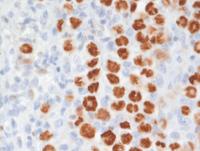

Sections from the right axillary lymph node demonstrate effacement of the lymph node architecture by a diffuse lymphohistiocytic infiltrate with patchy areas of necrosis and multiple vaguely perivascular clusters and singly scattered large Hodgkin-like cells with wreath-like nuclei somewhat reminiscent of lymphomatoid granulomatosis, grade 3.

The histologic features are intermediate between cHL, LyG grade 3 and T/HRLBCL without any areas displaying sheets of large centroblastic or immunoblastic cells.

Immunostains in GZL

Immunostains show that the large cells are uniformly positive for CD20, and Oct-2. Additional B-cell markers including CD79a, Pax5 (not shown) were also positive indicative of a well preserved B-cell program. The backgound is rich in CD3+ T-cells. There was also weak CD5 expression in the large cells (not shown). Rare large cells express weak CD30 but there is strong uniform CD15 with weak variable Mum1 (usually strong in pure cHL).